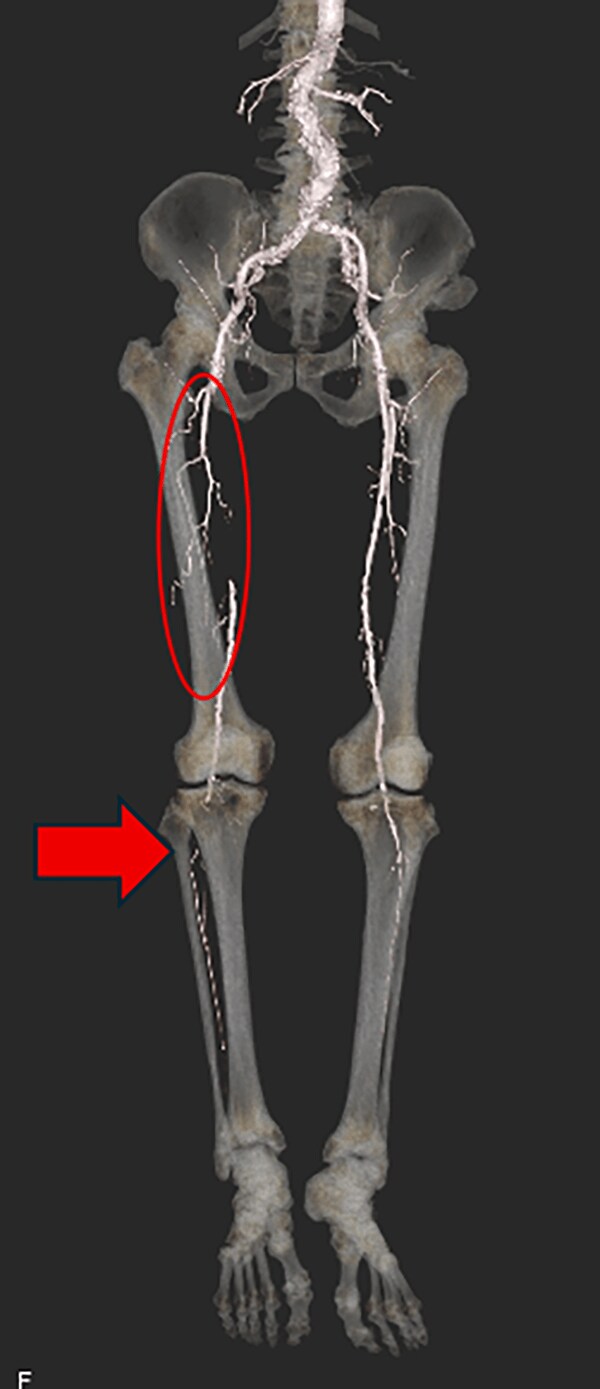

図3.大動脈~両下肢動脈3D-CTA VR像

大動脈から両下肢動脈の壁石灰化と口径不整を認める。右SFAは起始部から閉塞している(○)。右下肢動脈のrunoffが低下している(→)。